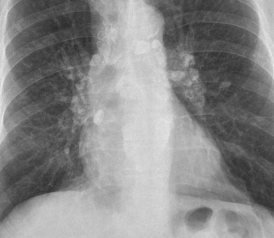

Silicosis

Paciente que ha sido expuesto a sepultación en arena y tiene este patrón

Silicosis aguda ( miliar )